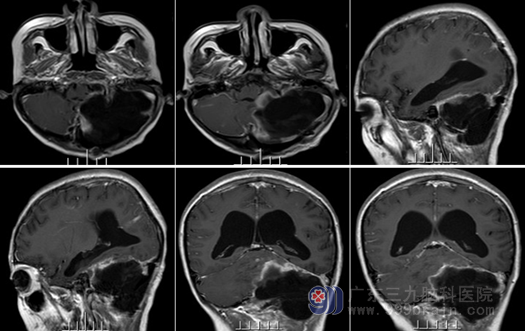

目前情况 :患者精神状态良好,生活自理。双侧眼球震颤,瞳孔不等,右侧瞳孔 3mm,直接间接对光反射灵敏,左侧瞳孔 4mm,直接间接对光反射迟钝,双侧视野缩窄,闭目难立征阳性,一字步征阳性,指鼻试验阳性。

头颅MR:左侧小脑半球发育不良性神经节细胞瘤切除术后改变,原病变已大部分切除。